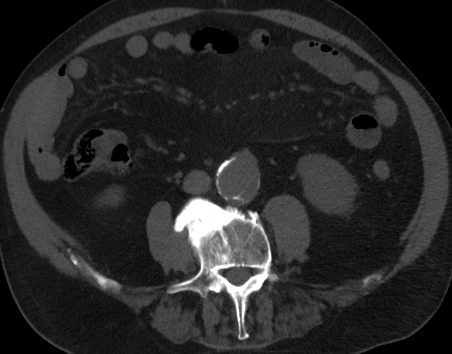

As we can see from Figure 3, the sequences have been anonymized, by converting the images from DICOM to the lossless portable network graphics (.png) format, pixel resolution, bit grey-levels.

At this point, the dataset is ready for the processing in the portal ImageLab. The latter, takes as input the basal ROI and its corresponding CM one, together with their respective binary masks. These, are used by the algorithm to create the image (see Fig. 2), and consequently to detect the vessel. As depicted in Fig. 4, in output the extracted image is provided, along with a colored map where green highlights pixels correctly classified by the algorithm, red indicates misclassified ones, and white indicates the areas the algorithm should have identified but did not. Adjacent to this, similarity indices described before are presented, computed by considering the CM image as the target, which is provided as input for this purpose. We have processed in the portal each slice of our dataset.